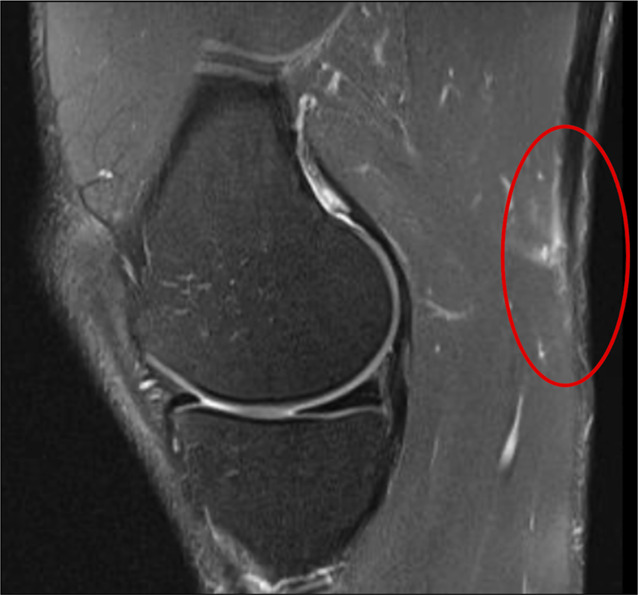

腿筋损伤是运动员常见的损伤,大多数损伤发生在肌肉腹部或近端肌肉肌腱连接处。远端腘绳肌病理相对不常见,但包括急性和慢性诊断的集合,可表现为膝关节内侧或外侧的症状,这是基于腘绳肌肌腱受累的情况。鹅肝粘液囊炎是最常见的远端腘绳肌病变,并伴有其他慢性诊断,包括腘绳肌内侧或股二头肌断裂。急性股二头肌骨折可以发生在孤立的方式,但大多数情况下发生在并发后外侧角损伤的高能创伤的结果。孤立性半腱肌破裂可发生在能量较低的急性事件中,通常发生在田径项目中。大多数远端腘绳肌病理可以不手术治疗,保守治疗效果良好。然而,急性撕脱伤往往需要手术干预,因为慢性问题不能充分响应长期保守治疗。由于远端腘绳肌损伤的发生率较低,因此远端腘绳肌损伤的治疗方法不如近端腘绳肌损伤发达。这篇综述的重点是远端腘绳肌损伤,目前的文献状态和治疗策略。

Hamstring injuries are a common injury sustained by athletes with most injuries occurring as strain injuries within the muscle belly or at the proximal musculotendinous junction. Distal hamstring pathology is relatively uncommon but comprises a collection of both acute and chronic diagnoses that can manifest with symptoms either on the medial or lateral side of the knee based on which hamstring tendons are involved. Pes anserinus bursitis is the most common of these distal hamstring pathologies with other chronic diagnoses, including snapping medial hamstrings or snapping biceps femoris. Acute biceps femoris ruptures can occur in an isolated fashion but most often occur in the setting of concomitant posterolateral corner injury as a result of high-energy trauma. Isolated semitendinosus ruptures can occur with lower-energy acute events, commonly with track and field events. Most distal hamstring pathology can be treated without surgery and do well with conservative treatment. However, acute avulsion injuries often require surgical intervention, as can chronic problems that do not adequately respond to prolonged conservative treatment. Treatment algorithms for distal hamstring injuries are less well-developed than more proximal injuries owing to their lower incidence. This review focuses on distal hamstring injuries, the state of current literature, and treatment strategies.